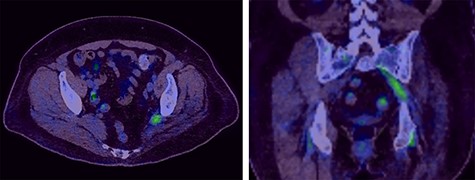

The PET CT scan findings were thickening of the left intra-pelvic portion of the sacral plexus (L5 and S1 nerve roots) up to the level of greater sciatic notch with associated increased activity as seen in Fig. 2.

Selected axial and coronal slices from PET scan showing increased activity in the left sciatic nerve.